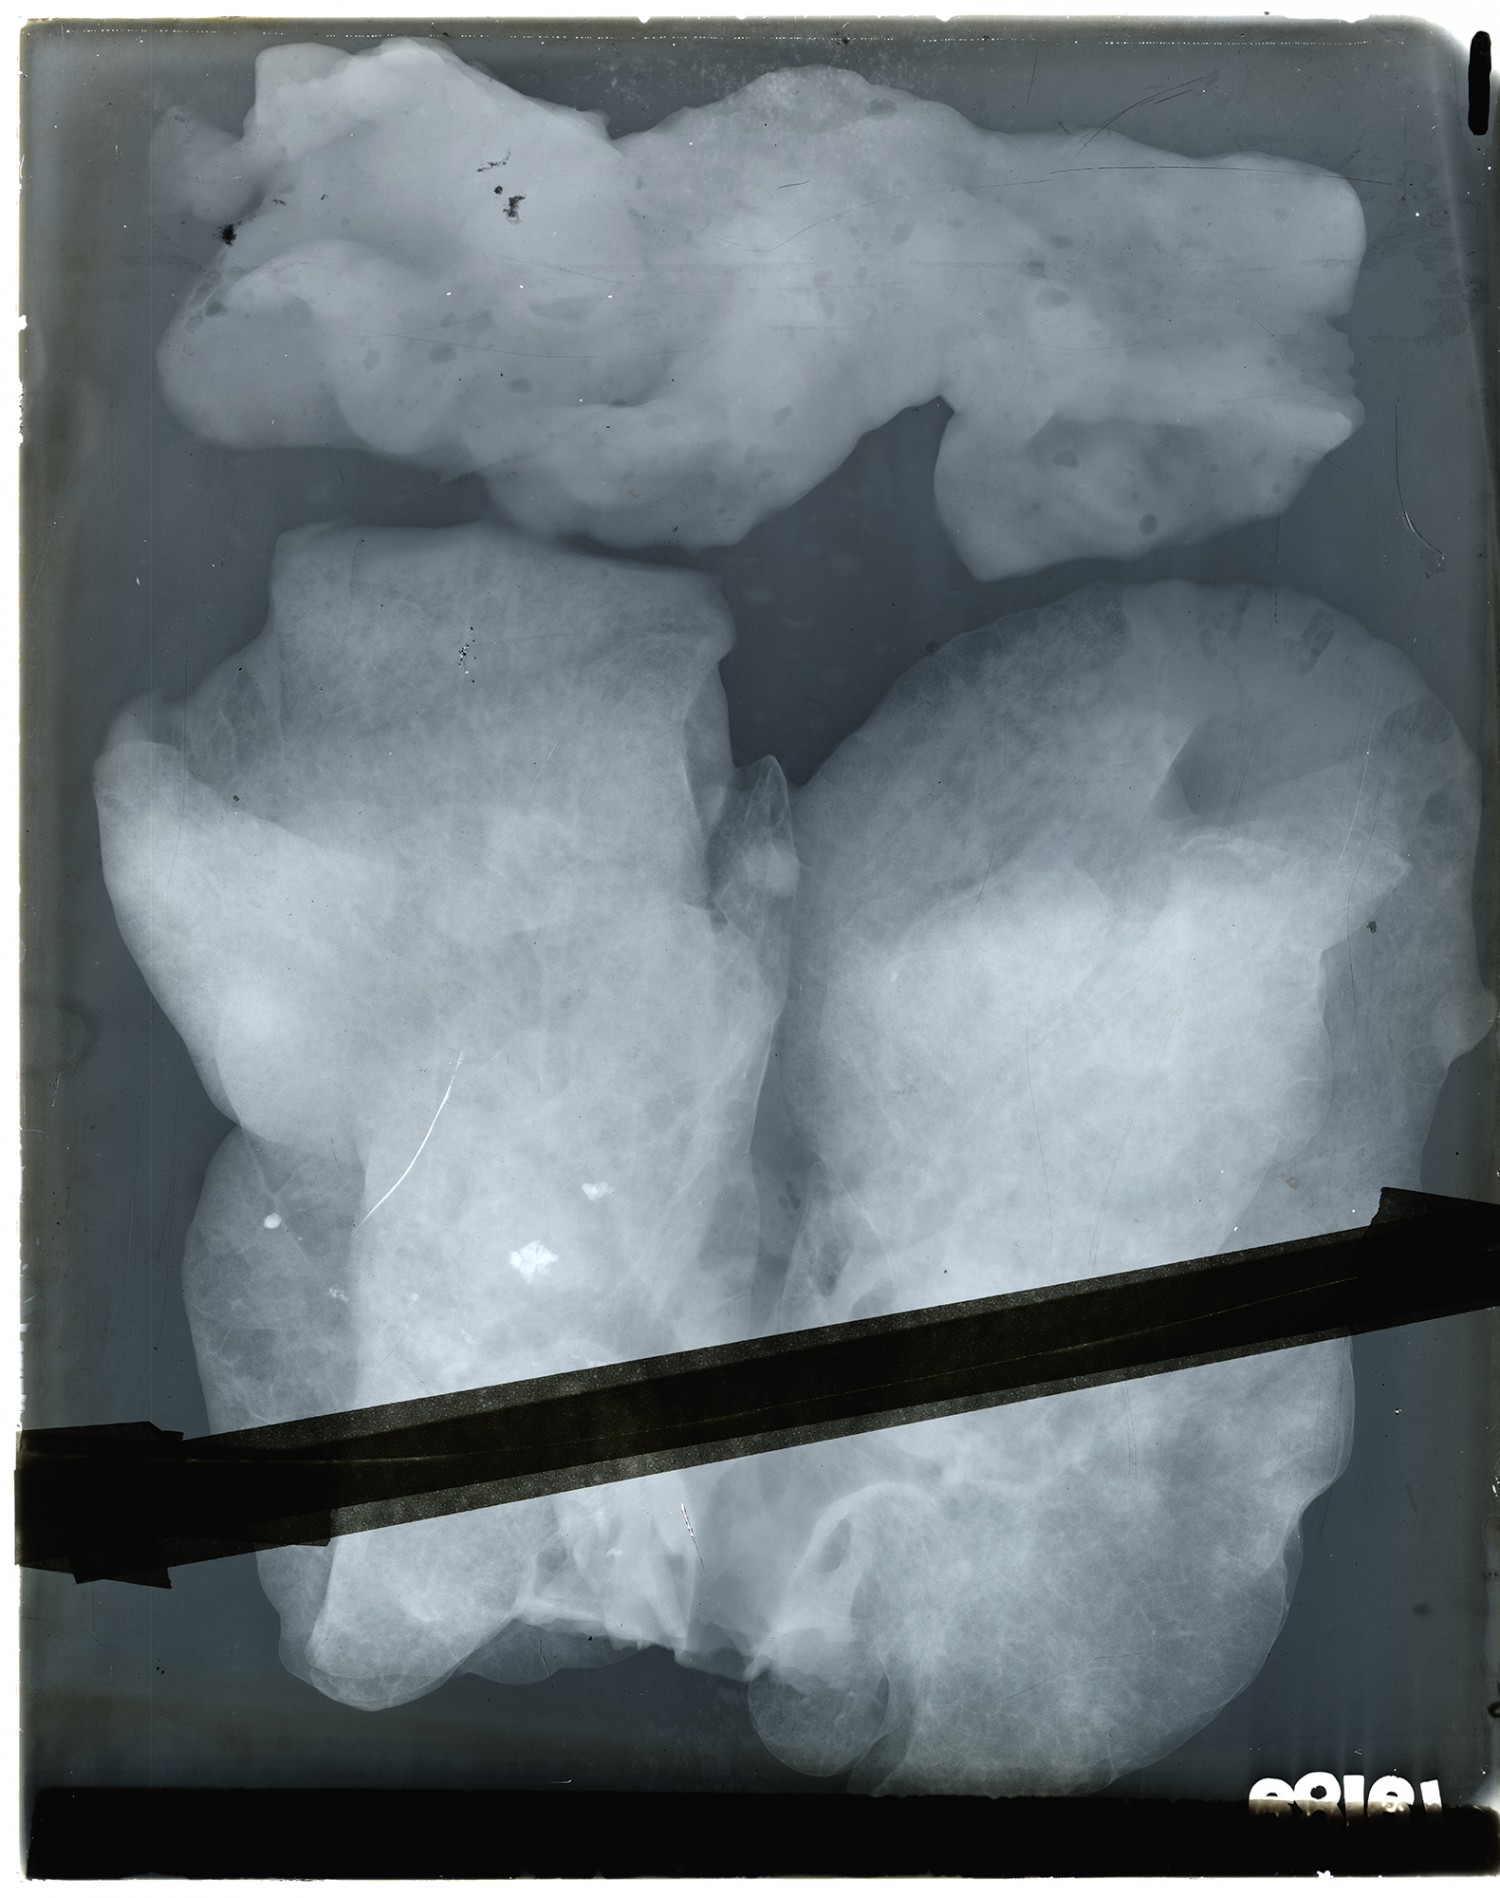

#17303 SHRAPNELL BALL LEFT THORAX. EMPYEMA